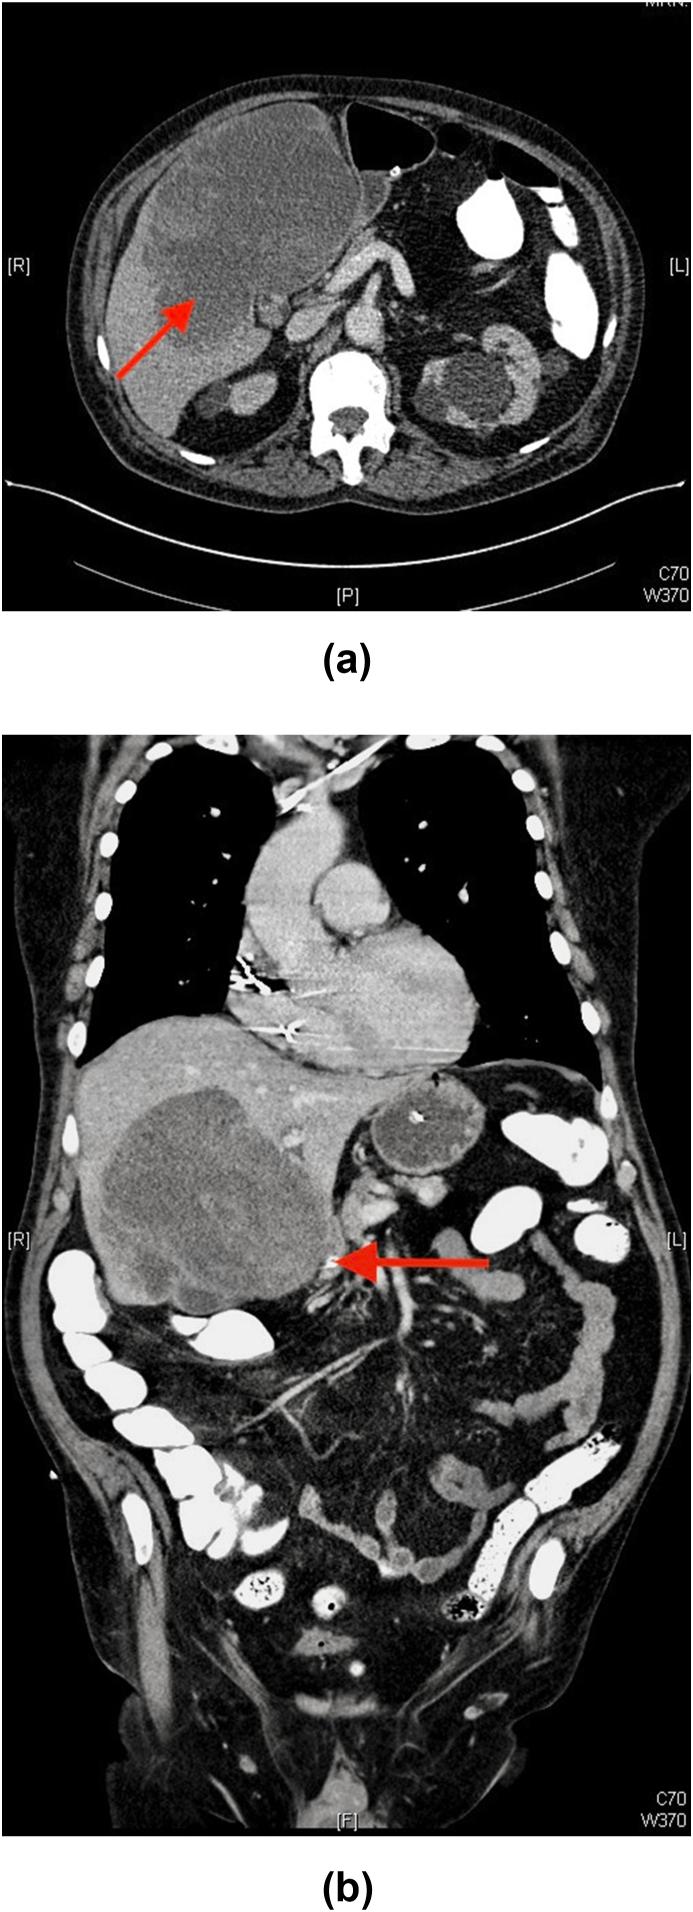

一名因前列腺癌转移导致肝内出血继发梗阻性黄疸的患者。

A patient with obstructive jaundice secondary to intrahepatic bleeding caused by prostate cancer metastasis.

A metastatic disease causes jaundice is not uncommon and usually related to direct tumor invasion to the biliary tree or massive intrahepatic metastasis. Cholestasis secondary to non-traumatic intrahepatic bleeding caused by metastasis from prostate cancer is never been reported in the literature. We present the first case of a-71-years-old patient developed Cholestasis due to spontaneous intrahepatic bleeding caused by metastasis from prostate cancer that was successfully treated conservatively. Prostatic cancer causes liver metastasis carries worse prognosis and compression of the intrahepatic biliary ducts can have long term unsatisfactory outcomes.

摘要

转移性疾病导致黄疸并不罕见,通常与肿瘤直接侵犯胆管树或大量肝内转移有关。文献中从未报道过前列腺癌转移引起的非创伤性肝内出血继发胆汁淤积的情况。我们报告了首例71岁患者因前列腺癌转移导致自发性肝内出血而出现胆汁淤积,经保守治疗成功治愈的病例。前列腺癌引起肝转移预后较差,肝内胆管受压可能导致长期不理想的结果。